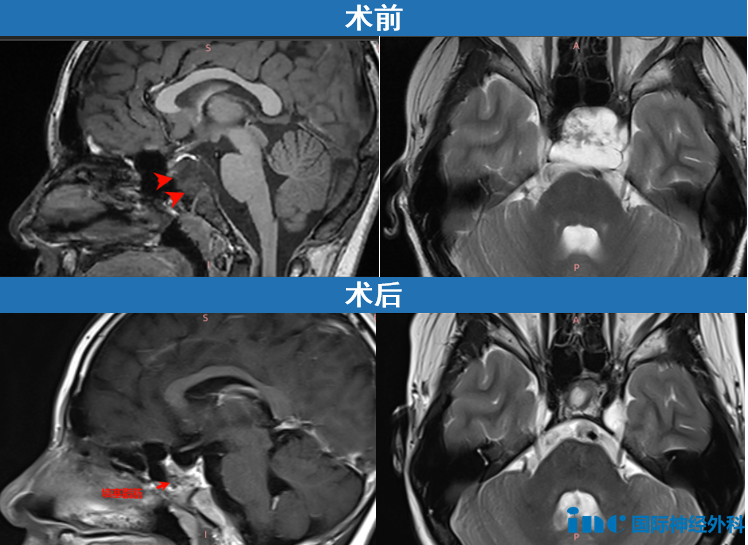

5年前,12岁患儿检查发现"占位性病变",因症状轻微选择保守观察。5年后头痛症状加重,复查发现颅底斜坡区33×26×33mm肿瘤病灶,侵犯左侧海绵窦,导致垂体移位及垂体柄受压变形。临床高度怀疑脊索瘤诊断。

症状加重结合病灶增大,此次需积极干预。经福洛里希教授手术治疗后,患者恢复情况良好。